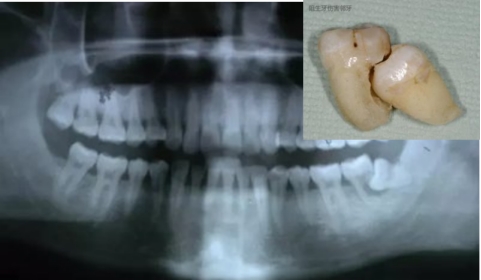

阻生牙(impacted teeth)是指部分萌出或完全不能萌出,且以后也不会自行萌出的牙。好发部位为下颌第三磨牙、上颌第三磨牙及上颌尖牙,其中阻生第三磨牙也叫做阻生智齿。

2、龋齿:阻生的智齿与第二磨牙之间容易积存食物残渣,而且不易清洁,很容易形成智齿和第二磨牙的龋齿而发生疼痛。

5、邻牙及支持组织的吸收:当阻生的智齿萌出过程中受阻于第二磨牙时,会引发第二磨牙牙根牙根逐渐吸收,严重者可使下颌第二磨牙远中牙根完全吸收,致第二磨牙松动、疼痛,常常食物嵌塞发生慢性牙周炎,也会造成牙槽骨的炎症性吸收,使第二磨牙反复肿痛。